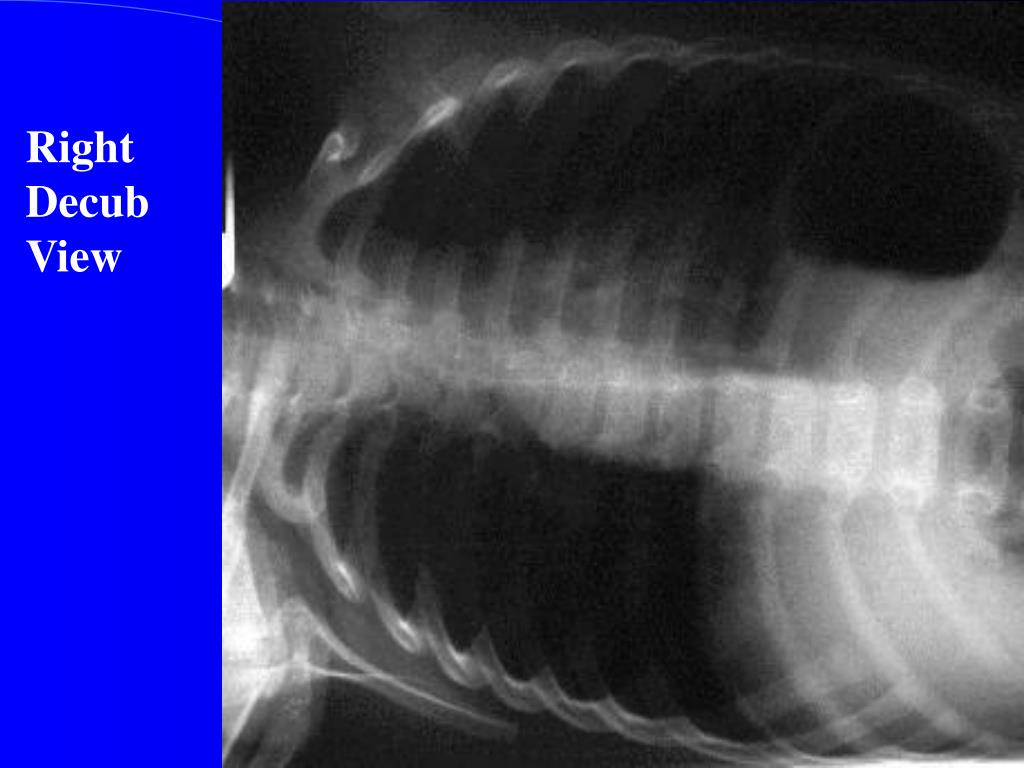

31. Right Decub View

34. Investigations • Xrays • Lateral neck • Chest – inspiratory, expiratory, decubitus views • Expiratory views • Overinflation (partial obstruction with inspiratory flow) • Volume loss with mediastinal shift towards obstructed • side (partial obstruction with expiratory flow) • Atelectasis (complete obstruction)

35. Decubitus views Normal Smaller volumes and elevated diaphragm on side down Abnormal Hyperinflation or “normal” volumes in decub position If suspected … Need a bronchoscope to rule out or remove Foreign Body